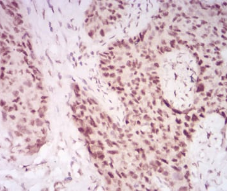

IHC    1/200 - 1/1000